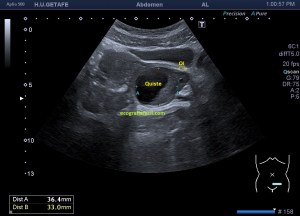

Bien, hemos visto una lesión que es un quiste hidatídico calcificado, pero te preguntarás, si nunca viste uno, ¿cómo es uno cuando tiene «hijas»?, es decir, cuando está activo…Mira este corte transversal de un hígado:

La LOE es de aspecto redondeado, heterogéneo, con multitud de pequeñas imágenes anecoicas e hipoecogénicas, de diferentes tamaños. Esta lesión fue estudiada también mediante otra técnica de imagen, la RMN donde se observa una imagen hiperdensa, con una amalgama de lesiones bordeando a periferia de la misma, de distintos tamaños como se objetiva en la imagen del mismo paciente, de la ecografía inmediatamente superior (Imagen 7). La lesión es activa, por tanto debió de ser tratada, la patología es potencialmente mortal en caso de que el quiste se rompiese.